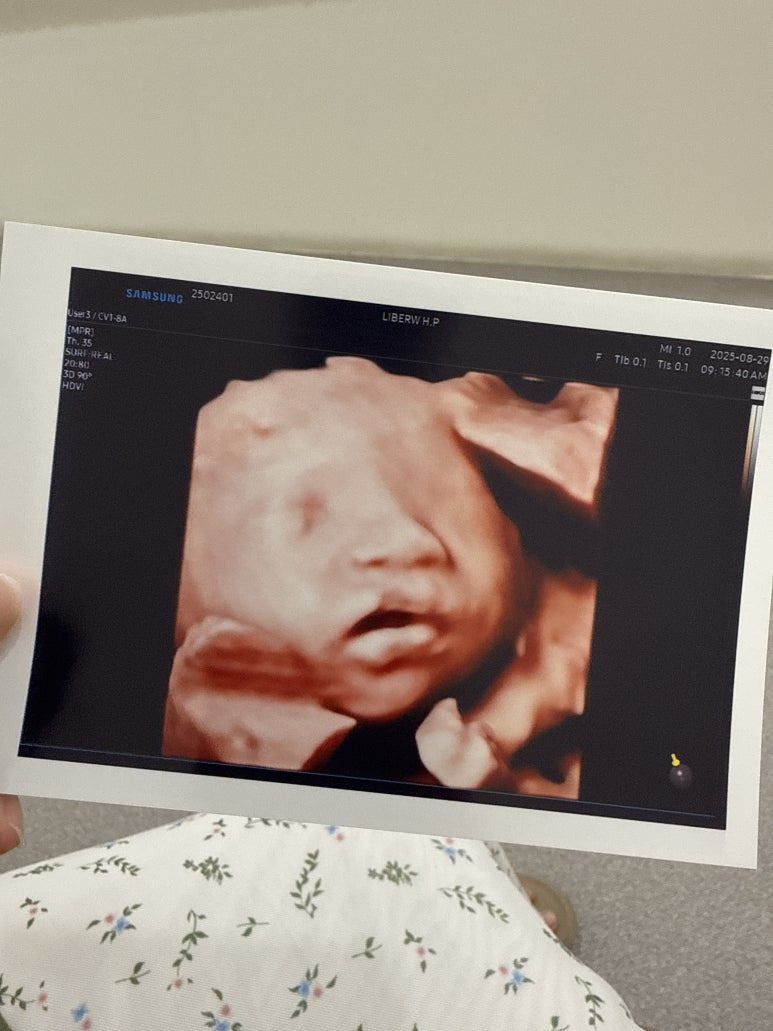

드디어 성공한 입체초음파

3차까지 실패하면 못본다해서 걱정했는데

성공했다 얏호👏👏

진짜 조~금 기대했는데,

사진 받으니까 너무 귀여워서 혼났다ㅠㅠ

손으로 턱 괴고 있었는데,

왤케 귀여운거니 사탕아...

나는 고슴도치맘이였다^^!!

내 최애사진은 입 벌린 사탕이ㅋㅋㅋㅋ

양수 마시는건지 입벌리고 있던게

딱 포착됬다 !!!

귀여워 죽겠네🤍🤍🤍